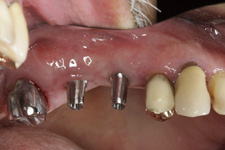

Během let může postupnou ztrátou zubů zůstat v ústech omezený počet zubů, které umožňují držení zubních náhrad.

V důsledku přetížení zbylých zubů např. houpavými pohyb snímacích náhrad dochází k uvolnění těchto zubů a držení můstků a protéz je tak velmi těžké. V těchto případech můžeme pomocí implantátů zvýšit počet pilířů a tím zabránit přetěžování a ztrátě zbylých zubů

S pomocí zubních implantátů můžeme díky různým kotevním systémům (třmeny, kulové hlavy, Locatory) zajistit stabilitu a držení protézy nebo při použití většího počtu implantátů zhotovit pevné náhrady – můstky nalepené nebo našroubované na pevno na implantáty.